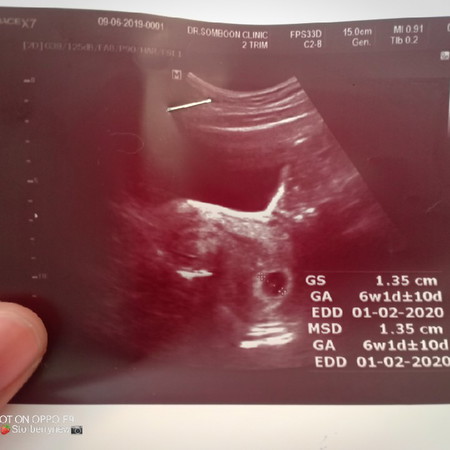

6วีค

ไปฝากท้องวันนี้ มีถุงตั้งครรภ์แล้วค่ะแม่ ยังไม่เจอตัวน้องและหัวใจ แม่บ้านไหนไม่เห็นตัวน้องบ้างค่ะ ก่อนน่านี้แม่เป็นท้องลมท้องแรก ท้องที่2เลือดออกยุติการตั้งครรภ์ ท้องที่3แล้วค่ะตอนนี้ ซาวด์ผ่านหน้าท้องน่ะค่ะ หมอบอกเห็นเงาตะคุ้มๆพอชื่นใจ ไม่อยากเสียน้องไปได้แค่หวังอยากเห็นหัวใจเล็กๆเหมือนบ้านอื่นค่ะแม่